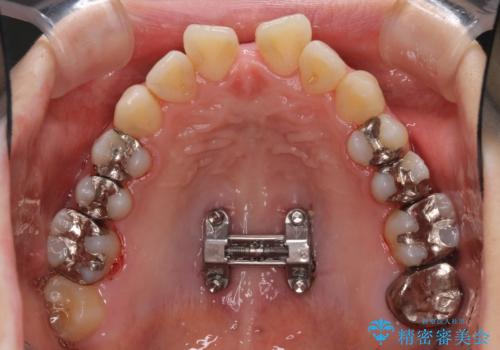

- 上下のデコボコと奥歯の咬みにくさを気にして来院された患者様です。

上顎骨の幅が下顎骨よりも小さいので、拡大装置により骨幅を広げて上下関係を改善し、その後インビザラインにて歯並びを整えることとしました。

上下の骨幅を改善したことで、スムーズに歯列矯正を行うことができました。